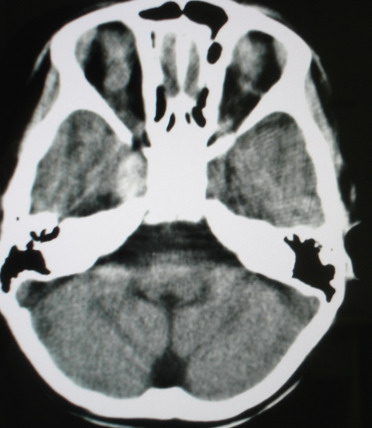

m/8y/,右侧眼睑下垂数日,发育良好,无外伤史,无头痛、恶心、呕吐,学习成绩良好。

ct意见:1、颅内血管畸形。2、右侧海绵窦血管瘤(颈内动脉海绵窦段动脉瘤)。3、脑萎缩。4、建议mr或dsa.

海绵窦瘘.注意眶内静脉有扩张.

右侧海绵窦血管瘤伴右侧海绵窦漏形成(由于右眼上静脉较左侧增粗。故考虑)。

支持 右侧颈内动脉海绵窦瘘.注意眶内静脉有扩张.